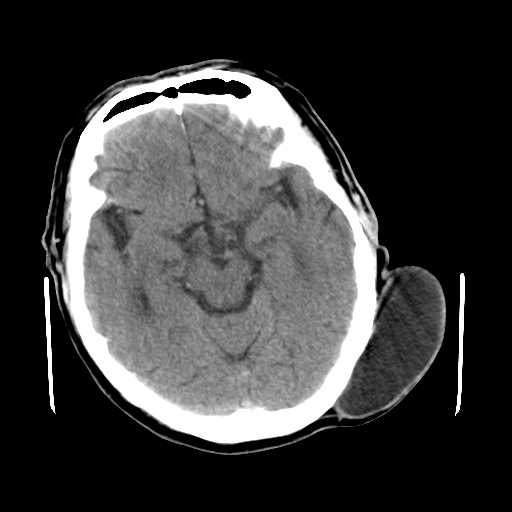

标题: CT25147:男,62岁,右侧肢体活动障碍不灵活三天。 [打印本页]

男,62岁,右侧肢体活动障碍不灵活三天,左侧头皮肿物十余年(ct值8hu)。

多发腔梗!皮下脂肪瘤!

1)多发性腔隙性脑梗塞。2)脑白质病。3)脑萎缩。4)左侧枕顶部头皮下皮样囊肿,不排除脂肪瘤。

1)多发性腔隙性脑梗塞。2)脑白质病。3)脑萎缩。4)左侧枕顶部头皮下皮样囊肿或表皮样囊肿。